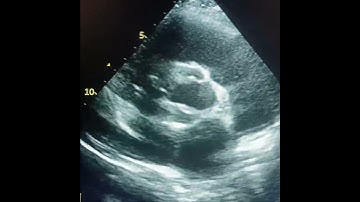

Short axis view at Aortic valve level l Pulmonary Valve Echo#shorts